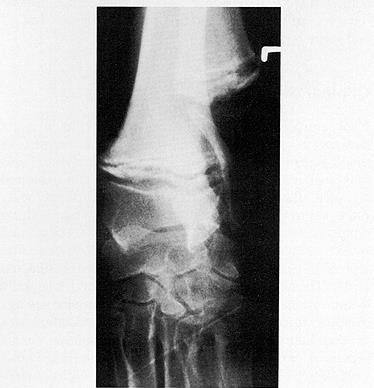

X光线通常显示病变骨头的变化,例如与生长板平行线的外观,骨密度的变化以及生长板周围的钙化。

5个月大的肥大性骨营养不良的大丹犬尺骨X光片